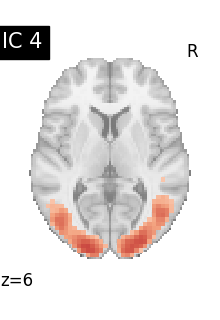

Finally, we plot the map for each ICA component separately

from nilearn.image import iter_img

from nilearn.plotting import plot_stat_map, show

for i, cur_img in enumerate(iter_img(canica_components_img)):

plot_stat_map(

cur_img,

display_mode="z",

title=f"IC {int(i)}",

cut_coords=1,

vmax=0.05,

vmin=-0.05,

colorbar=False,

)

show()